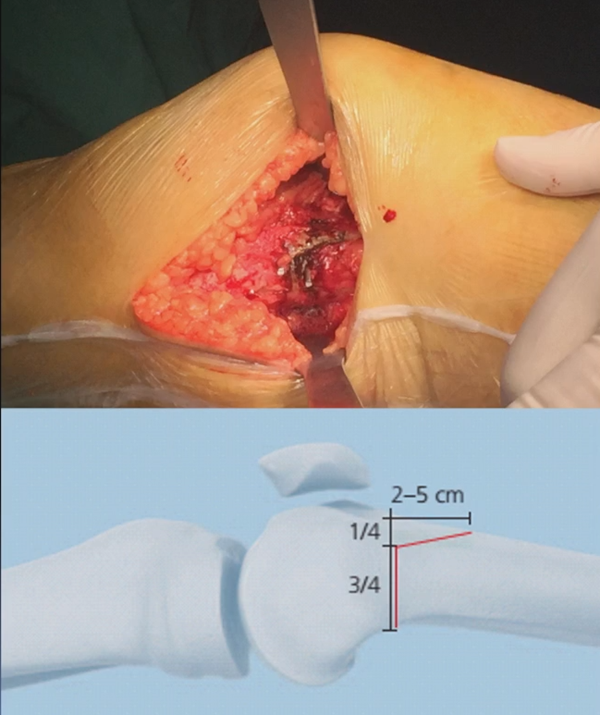

注意,目前临床推荐的DFO要求最好能做双平面截骨,即还要有一条上行截骨线,上行截骨线与水平截骨线夹角大概为95° 左右。这种截骨方式一方面可以增加稳定性,同时也可以减少对上方髌股关节的干扰。

上行截骨时,要保持肢体旋转中立位,前方要有骨撬保护,由内向外完全截开,上行截骨线不存在合页。

水平截骨时,同样放肢体中立位,后侧放一把骨撬保护后方重要结构。

截骨过程中,不要求一次截骨到位,把合页深度全部截到,可以留最后一点,用钻头由前向后打出一排筛孔来,把合页端弱化,再去做闭合时就不容易折断了。